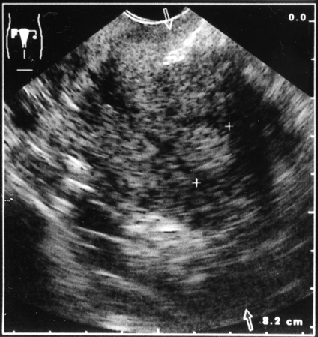

Клинико-морфологические и ультразвуковые параллели позволяют клиницисту на дооперационном периоде составить представление о степени распространения опухолевого процесса, наличия метастазов не только в зонах регионарного метастазирования, но и в органах брюшной полости (рис. 1–4).

Рисунок 3. Локализация опухоли в дне матки в виде полипа

Совпадение морфологических и сонографических данных о размерах первичной опухоли в матке и ее локализации отмечено соответственно в 86 и 45,7% наблюдений. Значительна частота совпадений и при большом поражении полости матки. Так, у 52,4% пациенток с тотальным поражением полости матки и у 88,2% пациенток с локализацией опухоли в полости матки с переходом на цервикальный канал данные УЗТ и гистологического заключения совпали. Этот показатель снижается до 15,8% при локализации аденокарциномы в области дна матки и ее трубных углов.